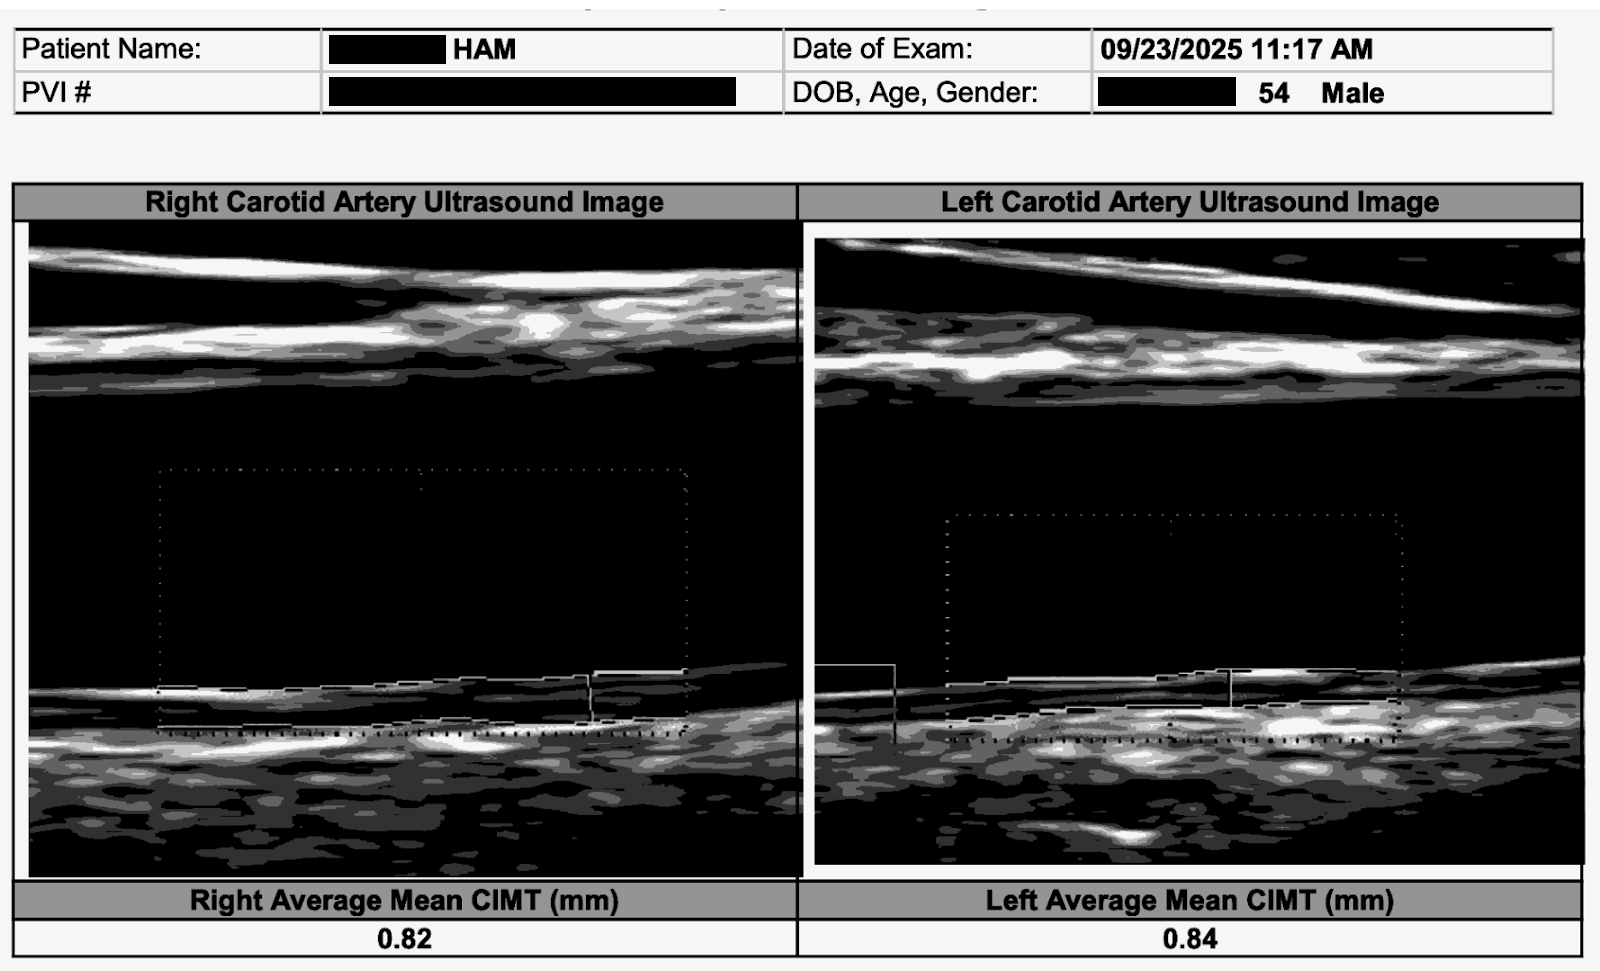

And here is what reversal looks like. My carotid plaque. Gone. Remodeled. In three months. Bilateral carotid IMT of 1.8 mm and 1.6 mm with visible plaque on both sides, dropping to 0.84 mm and 0.86 mm with no visible plaque detectable on ultrasound. My CT-FFR on a dominant D1 diagonal with 77 percent stenosis: improved from 0.75 to 0.80, crossing from ischemic into the normal range. LDL: 61, a 64 percent reduction. ApoB: 45. The word my physician friends used: Unbelievable!

After: Plaque remodeling and reversal. B-mode ultrasound imaging of the carotid artery. Kevin Ham, MD, 2025. Three months on the CAST protocol: WFPB diet, high-intensity cycling, structured fasting, targeted supplementation.

T: Track and Measure. Carotid IMT, CT-FFR, and coronary CT angiogram every six months. Lipid profile and metabolic profile every 30 to 45 days until you hit your targets, then every quarter. Without measurement, you are making changes into the void. Every image is a report from the front line.

2. Bilateral carotid CIMT reduced by 53 percent in the first three months.

3. All carotid plaque (~20%): gone.